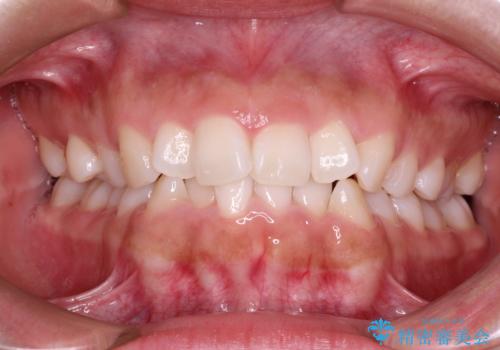

前歯の突出、深い噛み合わせ、ガタつきをマウスピース矯正(インビザライン)で治療した症例

- 初診時には上顎前歯の突出、前歯部の深いかみ合わせ、叢生が見られる状態でした。

インビザラインにて不正咬合の原因除去を行うシミュレーションを念入りに制作の上、治療を行いました。